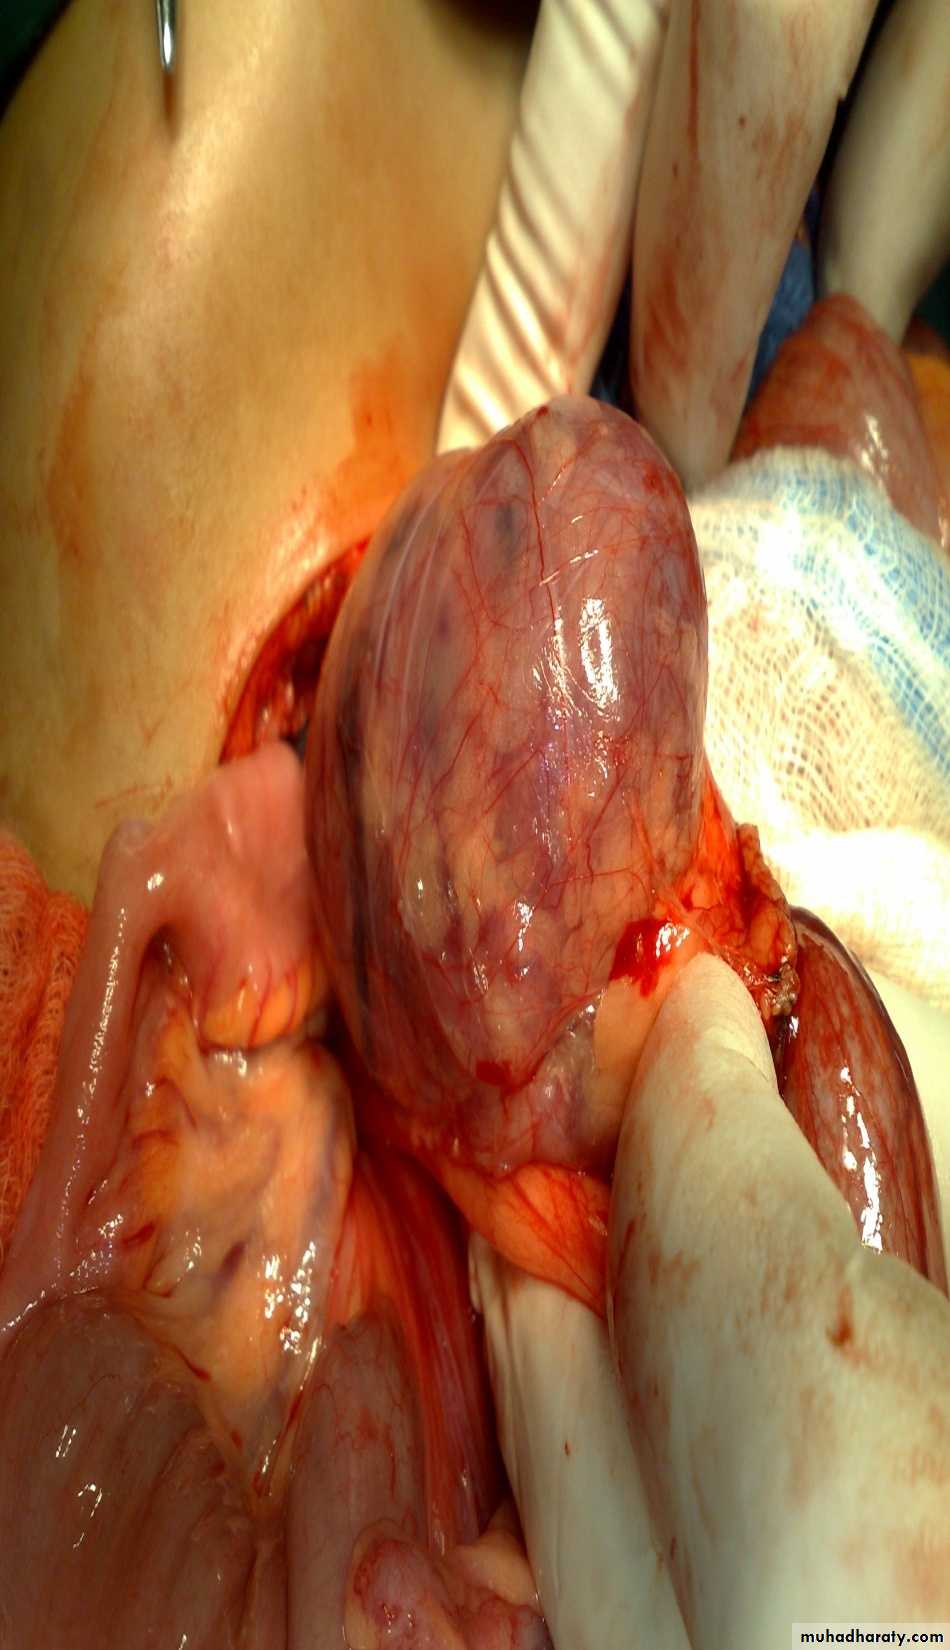

The Child with an Abdominal Mass

5 years child, presented with mass in the flank.

Dx: nephroblastomaDDx of mass in the flank:

Treatment by surgery remove the kidney + chemotherapy